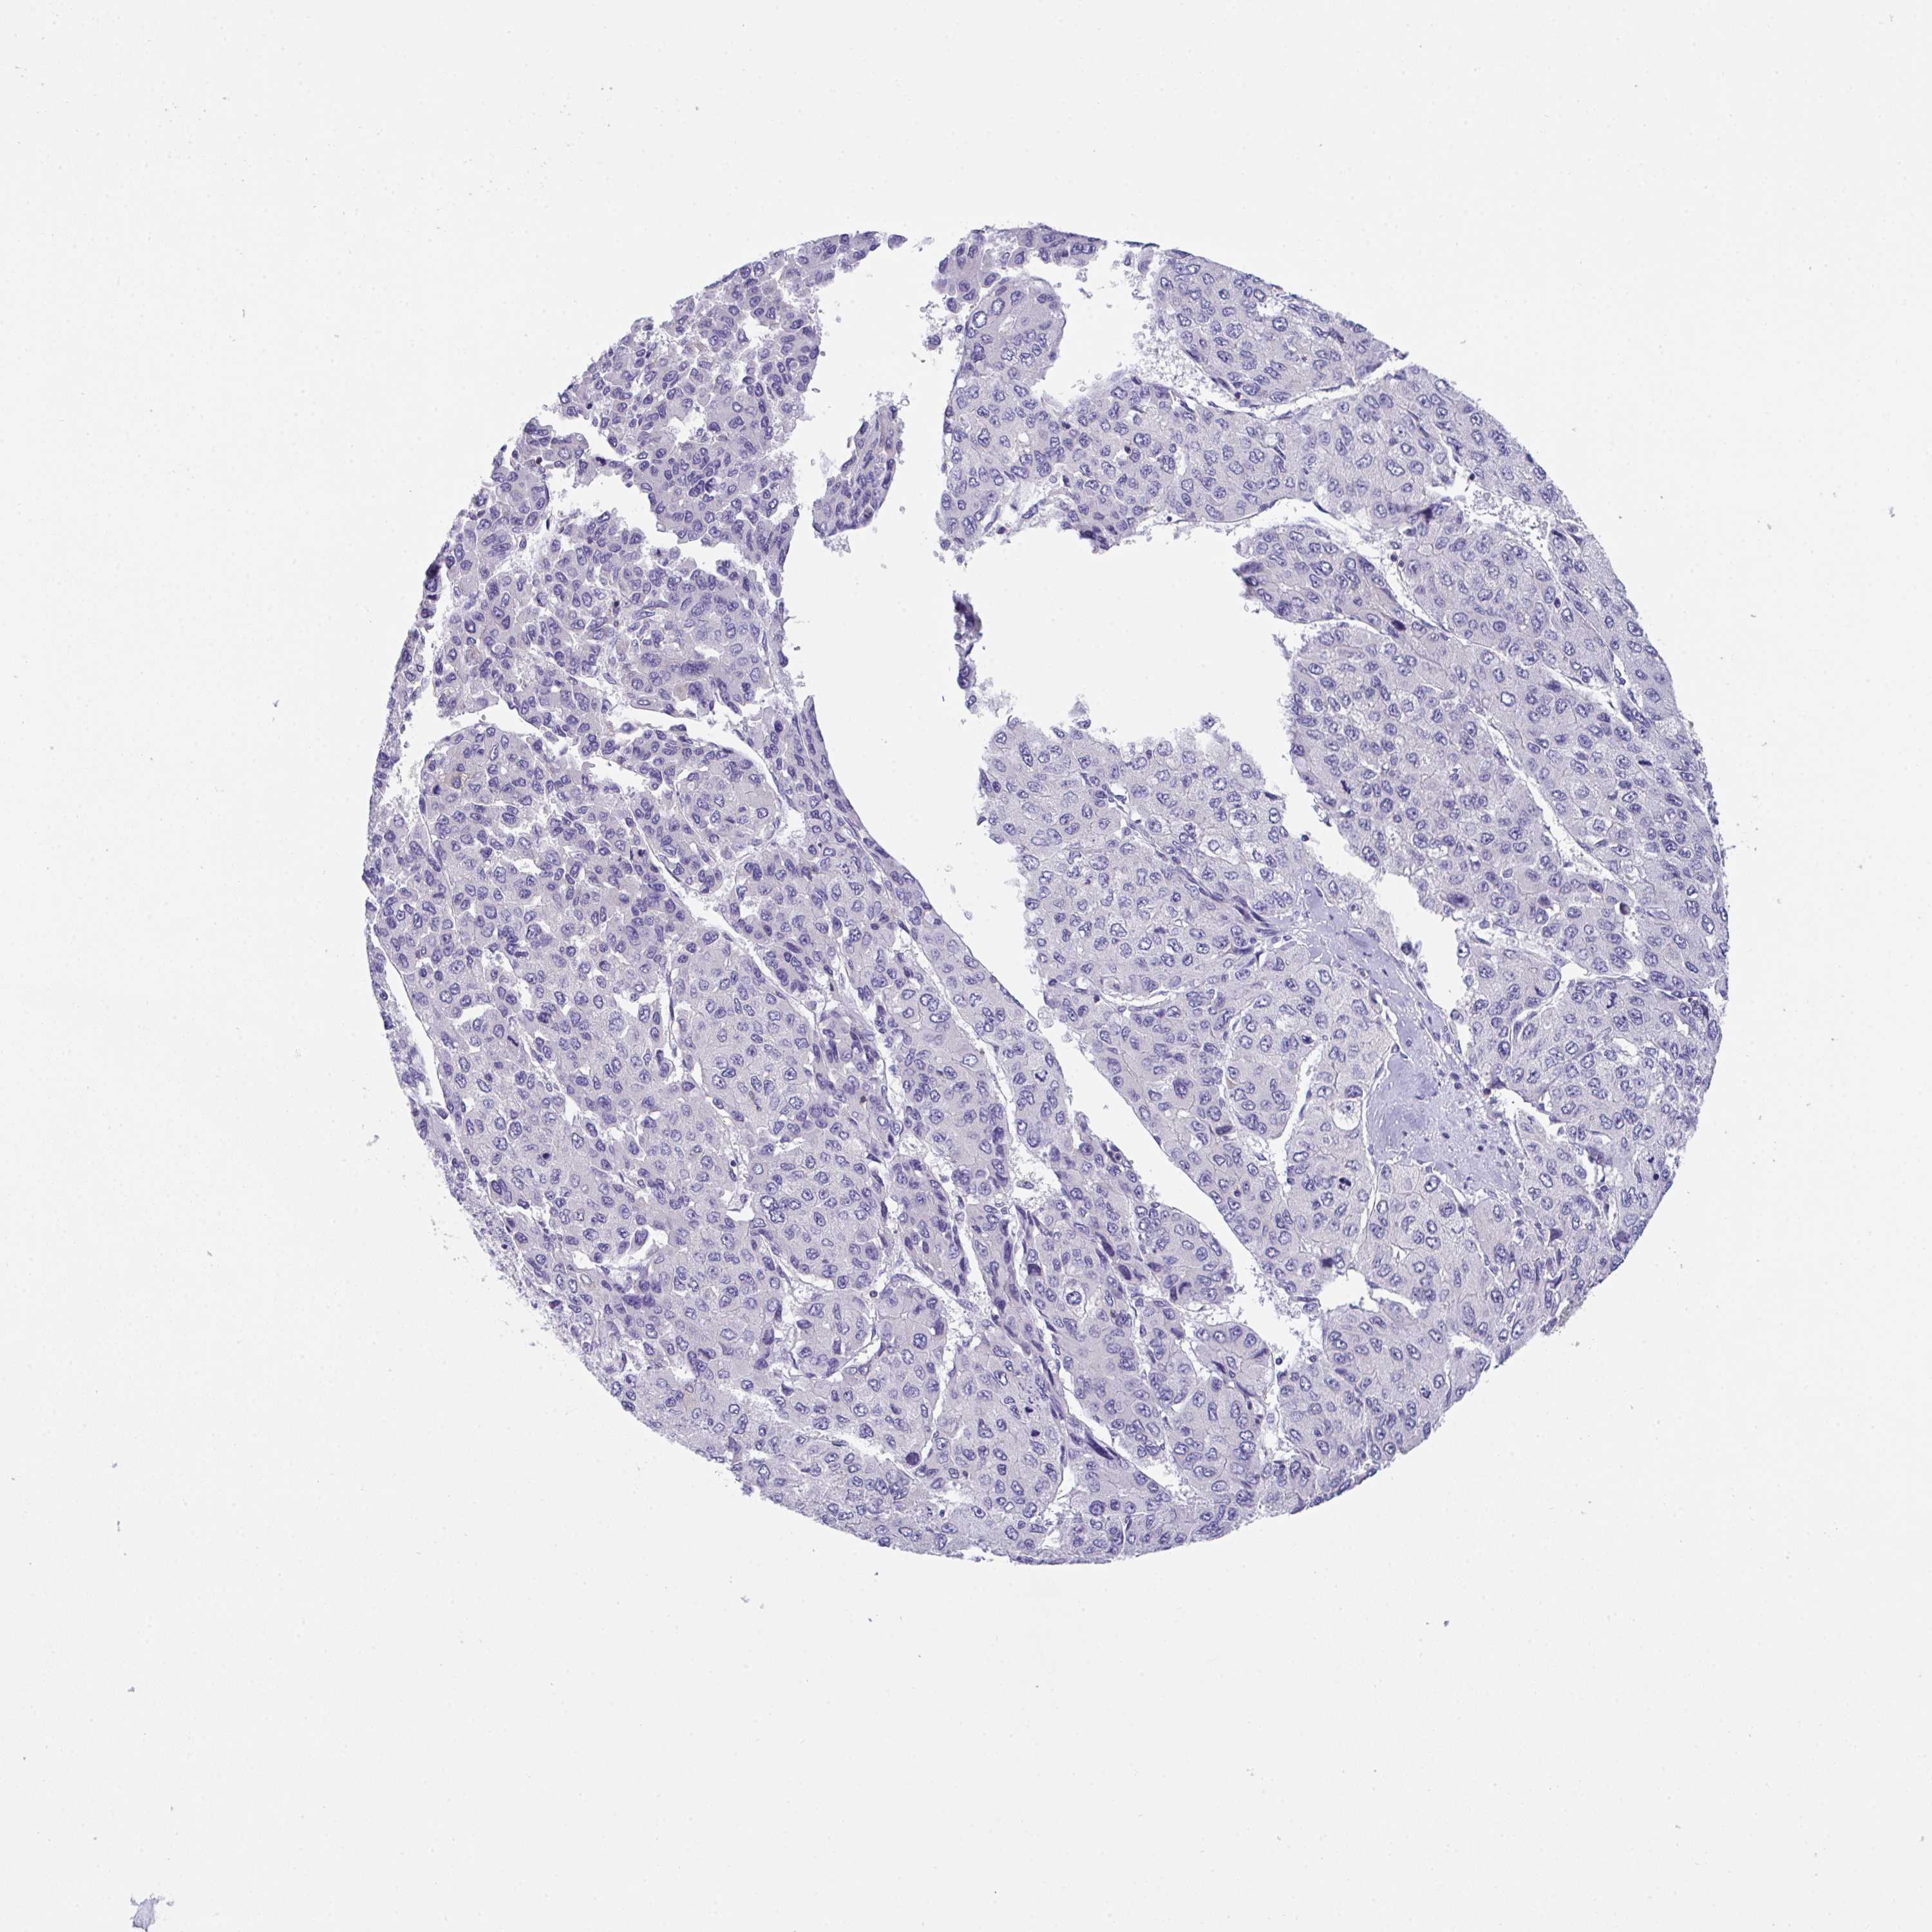

LIVER CANCER - Protein expressioni

A mouse-over function shows sample information and annotation data. Click on an image to view it in a full screen mode. Samples can be filtered based on level of antibody staining by selecting one or several of the following categories: high, medium, low and not detected. The assay and annotation is described here.

Note that samples used for immunohistochemistry by the Human Protein Atlas do not correspond to samples in the TCGA dataset.

Antibody stainingi

Antibody staining in the annotated cell types in the current human tissue is reported as not detected, low, medium, or high, based on conventional immunohistochemistry profiling in selected tissues. This score is based on the combination of the staining intensity and fraction of stained cells.

Each image is clickable and will lead to virtual microscopy that enables deeper exploration of all samples and also displays staining intensity scores, fraction scores and subcellular localization as well as patient and tissue information for each sample.

Antibody HPA055922

Antibody HPA056816

Staining

High

Medium

Low

Not detected

Intensity

Strong

Moderate

Weak

Negative

Quantity

>75%

75%-25%

<25%

None

Location

Nuclear

Cytoplasmic/membranous

Cytoplasmic/membranous,nuclear

Carcinoma, Hepatocellular, NOS

Cholangiocarcinoma